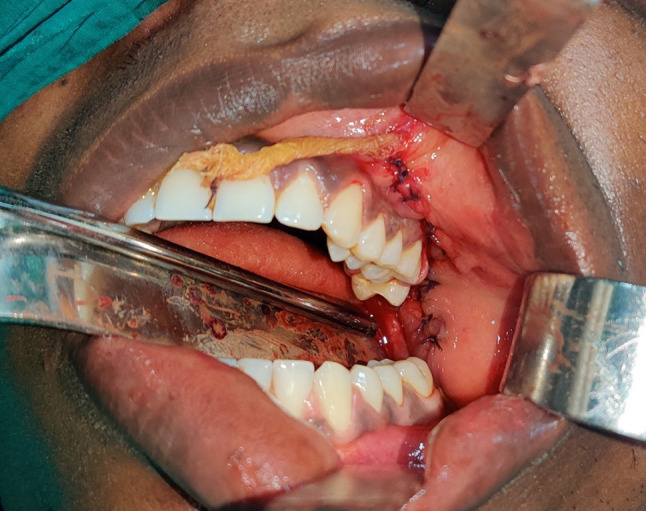

Fig. 3.

Intraoperatively, a maxillary vestibular incision was made and the tumour was exposed

Fig. 4.

Blunt dissection carried out and tumour mass being excised